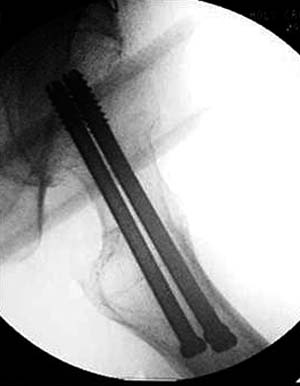

Или всё таки красивее было бы вот так? И при нагрузках динамизация по винту?